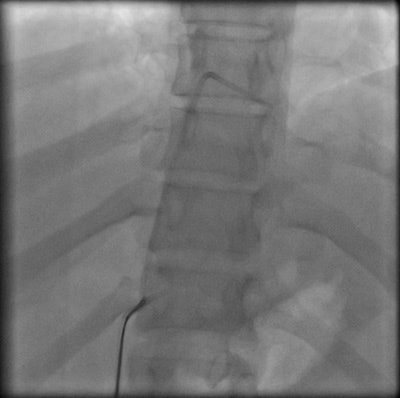

Percutaneous retrieval of the retained fragment of the fractured portacath catheter was successfully accomplished on the second attempt. Following prepping of the right groin, the right femoral vein was punctured and an 8 French sheath was inserted. Selective catheterization of the right ventricle was performed using a 6 French catheter. A 25-mm snare was used to capture the migrated retained fragment. It was then removed successfully without immediate complications.

The postoperative radiograph showed no residual fragments.

Postoperative chest radiograph.Discussion